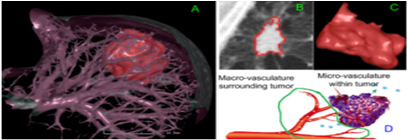

肿瘤的定量分析与评估

该方向基于影像组学进行癌症(肿瘤)防诊治方案的精准化研究。针对乳腺癌、肺癌等癌症风险评估、早期诊断以及预后评估在影像学上的需求,重点研究和优化计算机辅助诊断程序,实现多模态影像更准确的图像分割,完成基于多模态影像的肿瘤或病变区域以及周围组织的多维图像特征(包括型态学,纹理学和密度的不均匀性等特征)计算;结合生物基因特征,综合分析能够反映生物基因特征的多模态影像表型特征,通过应用深度学习(Deep Learning)理论和方法对影像特征进行优化选取,建立以人工智能为基础的分辨器,构建基于这些不同模态影像特征参数的癌症早期诊断或近期发病风险预测模型,进而帮助寻找与癌症精准预测、早期诊断、分类分型及预后判断相关的影像组学特征谱,并实现更为精确和精细的疾病分类、分型,为患者精确诊断和精确治疗的标准化提供依据。